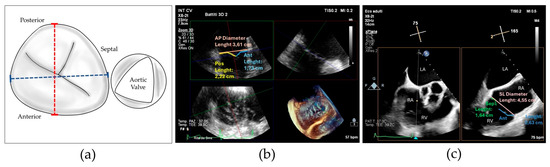

We believe that our results can be particularly useful in planning the interventional procedure, especially in patients with complex tricuspid valve anatomies, who may require posterior grasping to optimize procedural outcomes (see Figure 5).

Figure 5. (a) Transesophageal echocardiographic in the 3D zoom modality showing complex tricuspid valve morphology; (b) the same valve after repair with implantation of three devices individuated by asterisks.